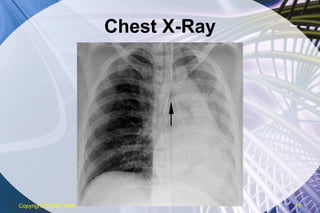

Secondary Methods Presence of exhaled CO2 Colorimetric Capnography Aspiration of air from ETT EDD Chest X-Ray Assures proper height above carina Copyright  © 2007 ENA

Chest X-Ray Copyright  © 2007 ENA